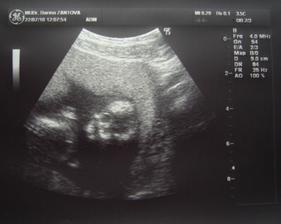

31.8. Velký utz u mojí dr. Vše je v pořádku a čekáme chlapečka.

13.9. Velký utz u Mudr. Břeštáka. Potvrzen chlapeček a váhový odhad podle utz je 429g.